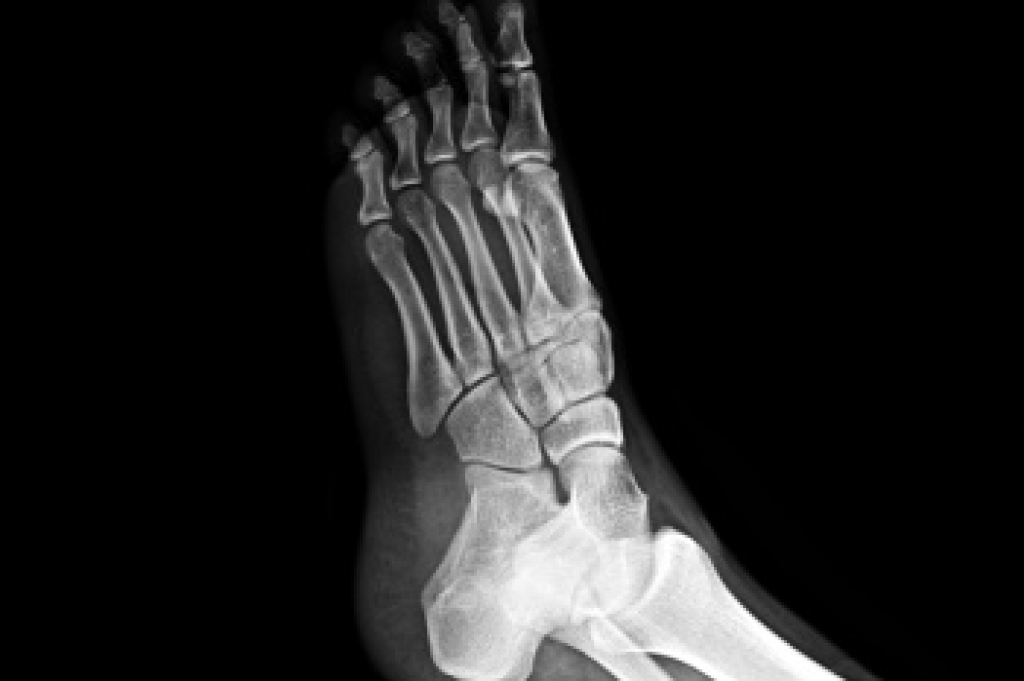

A metatarsal stress fracture is a tiny crack in one of the long bones of the foot, often caused by repetitive stress or overuse during activities like running or jumping. Symptoms include localized pain, swelling, and tenderness that worsens with activity. Preventing metatarsal stress fractures involves gradually increasing activity levels, wearing supportive footwear, and incorporating rest days into your exercise routine. Proper warm-up and stretching before activities can also reduce the risk. Treatment typically includes rest, icing the affected area, and using orthotics or supportive footwear to relieve pressure on the foot. In severe cases, immobilization with a cast or walking boot may be necessary. A podiatrist can conduct a thorough evaluation, possibly using imaging studies, and recommend appropriate treatments to promote healing and prevent further injury. Early intervention can speed up recovery and prevent long-term complications. If you suspect a metatarsal stress fracture or experience persistent foot pain, it is suggested that you make an appointment with a podiatrist.

To figure out the cause of foot pain, podiatrists utilize several different methods. This can range from simple visual inspections and sensation tests to X-rays and MRI scans. Prior medical history, family medical history, and any recent physical traumatic events will all be taken into consideration for a proper diagnosis.